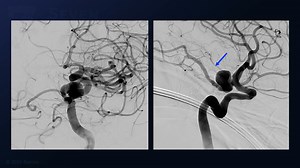

Kraniektomie - Aneurysm